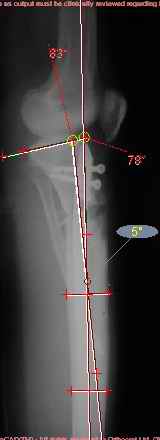

Продолжение обсуждения, начатого в октябре прошлого года (см. здесь) Наконец-то оперировали эту пациентку. Биопсию сделали - опухолевого ничего нет. Пока все участвовавшие в обследовании смежные специалисты и ортопеды сошлись, что это молокальная монооссальная фиброзная дисплазия. 20 марта наложили аппарат, сделали чрескожную остеотомию. К 3 апреля все докрутили. Сегодня заштифтовали. Начальные и итоговые снимки в приложении. Рекурвацию можно было еще немного больше устранить, и чуть кзади сместить диафиз. Но вроде и так ничего выглядит, по сравнению с тем, что было. Комментарии приветствуются.

ничего не понимаю в детской и ортопедии, но в боковой проекции нет рекурвации,

а даже немного гиперкоррекция, что по-моему есть хорошо. Кортикалы по задней стенке совпадают, диафиз на одну неправду кзади.